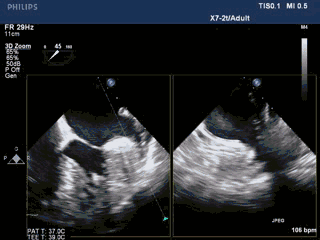

术中TEE双平面及DSA造影显示,梳状肌发达,延伸至心耳口部。

DSA造影显示LAA开口直径18mm,深26mm,拟采用24mm Watchman封堵器。